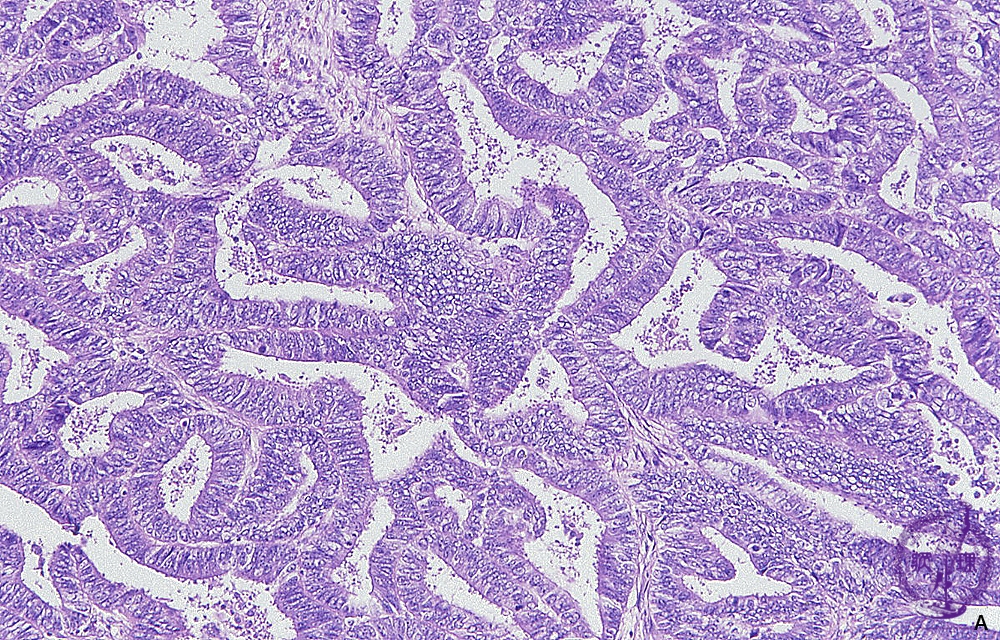

子宮頸部の腺がんは、子宮頸部内の腺細胞から発生します。子宮頸管内膜は、子宮につながる内膜の内側部分を形成します。

- 生検:医師は、がんの有無を確認するために子宮頸部組織のサンプルを採取する生検を指示する場合があります。